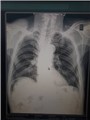

Dấu hiệu Chilaiditi của bệnh nhân Đ.T, 91 tuổi thăm khám tại bệnh viện Đa Khoa Nghi Xuân.